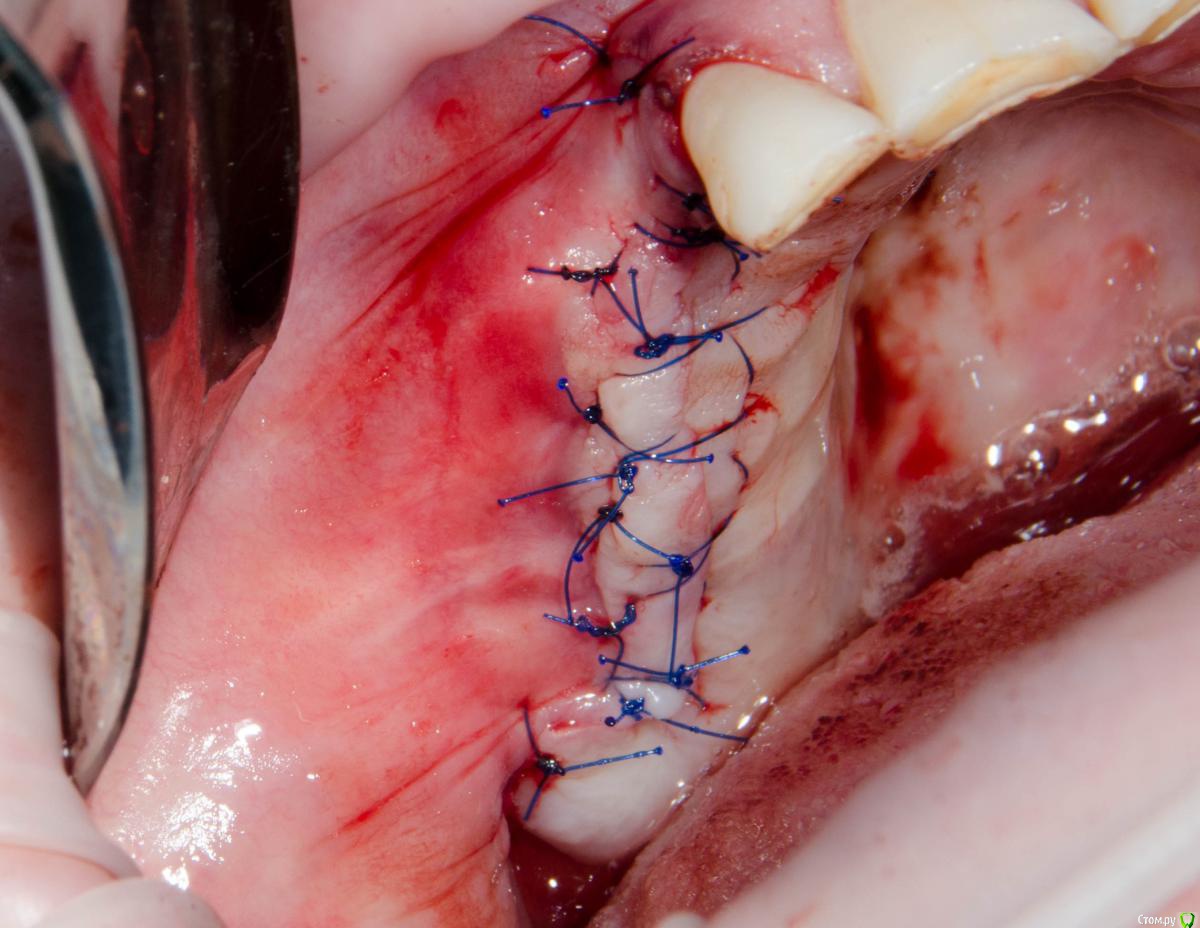

kamranchick Опубликовано 4 мая, 2018 Поделиться Опубликовано 4 мая, 2018 Обратился пациент после очередной халтуры которыми радуют меня коллеги из соседних клиник)фотопротокол ни как у Сашки Гудкова но более-менее понятно))Обратился пациент, в соседней клинике удаляли зуб, корень протолкнули в пазуху, далее пациент попал в ЧЛХ, там сделали радикальную гайморотомию, все достали, и вот попал пациент ко мне, так как в другой клинике сказали что у вас тут залу*а, а не кость, ну и погнали.1. пытался остро отслоиться, перфа на перфе, закрывал prf, мембранами, губками, стики бон + синус имплантация. ожидание 9 месяцев2. Пластика мягких тканей ожидание 2 месяца. 13 Ссылка на комментарий

Kazankov.Egor Опубликовано 5 мая, 2018 Поделиться Опубликовано 5 мая, 2018 Обратился пациент после очередной халтуры которыми радуют меня коллеги из соседних клиник)фотопротокол ни как у Сашки Гудкова но более-менее понятно))Обратился пациент, в соседней клинике удаляли зуб, корень протолкнули в пазуху, далее пациент попал в ЧЛХ, там сделали радикальную гайморотомию, все достали, и вот попал пациент ко мне, так как в другой клинике сказали что у вас тут залу*а, а не кость, ну и погнали.1. пытался остро отслоиться, перфа на перфе, закрывал prf, мембранами, губками, стики бон + синус имплантация. ожидание 9 месяцев2. Пластика мягких тканей ожидание 2 месяца.К кому сходить на мягкие ткани? Посоветуйте пожалуйста. Ссылка на комментарий